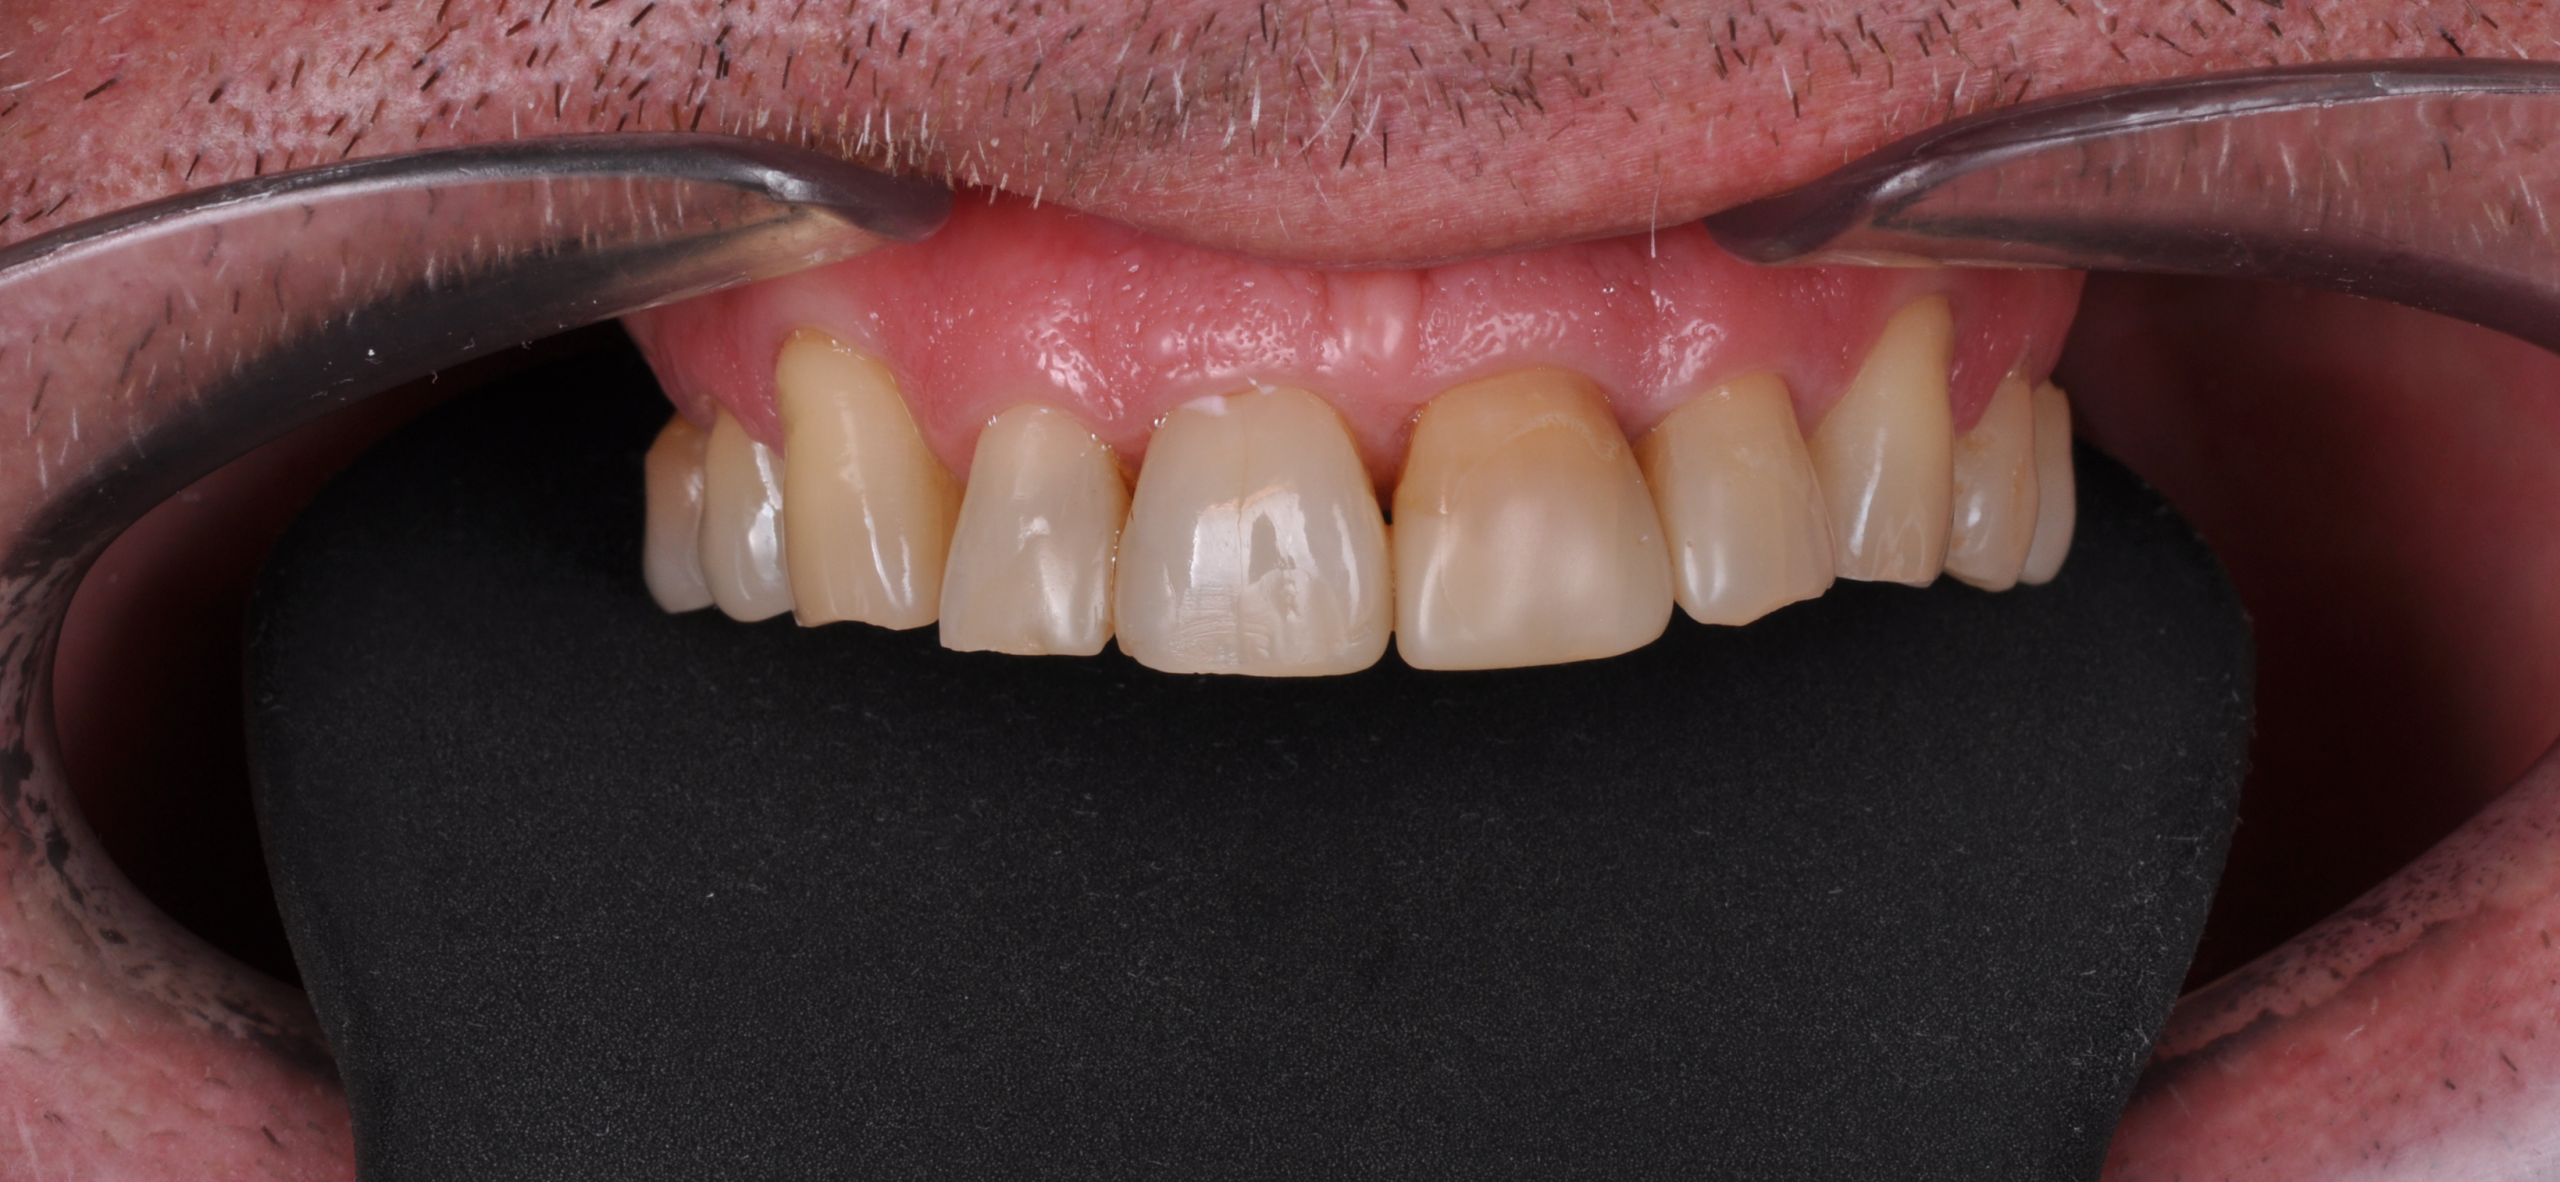

Doar astfel putem crea profilul de emergență corect al coroanei dentare, ceea ce permite conformarea papilei și a sulcusului.